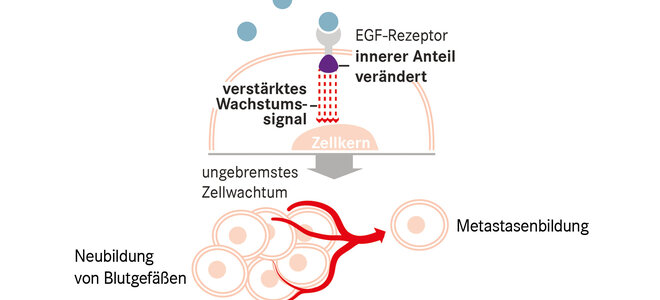

Krebs entsteht, wenn Zellen sich aufgrund genetischer Änderungen ungebremst vermehren. Manchmal lassen sich diese an bestimmten Stellen der DNA festmachen. Dort werden Bausteine ausgetauscht, ganze Abschnitte umverlagert, fusioniert oder vermehrt. Etwas unscharf spricht man dann von „Treibermutationen“, die der Entartung zugrunde liegen. Bei Ärztinnen und Ärzten laufen sie unter ihren Abkürzungen wie ALK oder KRAS.

Bei der häufigsten Unterform des nicht kleinzelligen Lungenkrebses, dem Adenokarzinom, sind diese DNA-Umformungen für rund zwei Drittel aller Fälle verantwortlich. Steht die Ursache fest, ist auch der Weg zur Therapie nicht mehr weit. Für acht Treibermutationen sind bereits Medikamente zugelassen. Zu etlichen weiteren laufen Studien. Rund 40 Prozent der Adenokarzinome lassen sich bisher mit den „-tinib“ behandeln, auf das all diese Mittel enden. Doch fast alle der zielgerichteten Medikamente kommen erst in einem fortgeschrittenen Krankheitsstadium zum Einsatz, wenn klassische Therapien versagen. Eine Heilung ist dann nicht mehr möglich. Aber teils eine Lebensverlängerung.

Am besten untersucht ist dies für EGRF-Mutationen, Ursache für rund 15 Prozent der Adenokarzinome. Osimertinib, der neueste unter mehreren Wirkstoffen gegen diesen Typ, verlängerte die Zeit bis zum Fortschreiten der Krankheit auf 19 Monate; nach 18 Monaten lebten noch 83 Prozent der Patientinnen und Patienten.